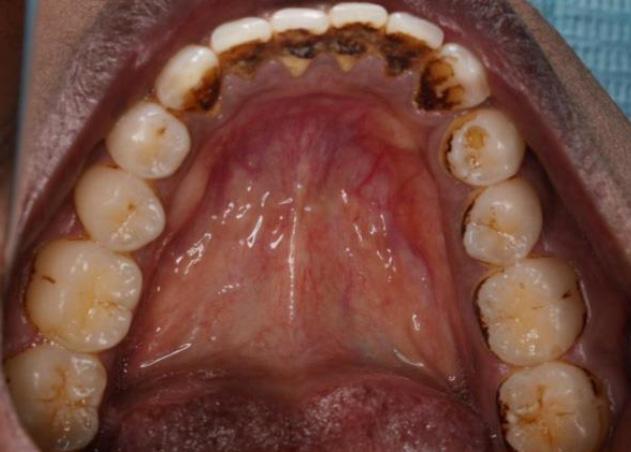

Apa itu rawatan penskaleran gigi?

Pernahkah anda ke mana-mana Pusat Pergigian Angkatan Tentera (PGAT) atau ke klinik pergigian di mana ramai doktor gigi menasihatkan anda untuk melakukan penskaleran gigi yang juga dikenali sebagai scaling? Penskaleran adalah prosedur menghilangkan tartar (plak yang mengeras) dan kotoran yang melekat pada gigi anda kesan daripada makanan, rokok atau teknik pemberusan yang kurang efektif. Rawatan ini adalah salah satu cara untuk mencegah dan merawat penyakit gusi jika doktor gigi telah mengesahkan anda mempunyai plak pada gigi.

Oleh kerana makanan sering berada di celah-celah atau ruang di antara gigi, lama kelamaan makanan tersebut menjadi tartar dan tidak dapat dicuci menggunakan berus gigi biasa. Maka dengan itu, lama-kelamaan ruang tersebut tertutup dan anda akan merasakan tiada ruang dicelah permukaan gigi. Setelah rawatan penskaleran ini dilakukan, kesihatan gusi anda akan menjadi lebih baik dan anda akan merasakan tanda-tanda penyakit gusi seperti gusi mudah berdarah sewaktu memberus gigi akan berkurangan.

OLEH Maj (Dr) Tengku Natasha Eleena binti Tengku Ahmad Noor (801 RSAT Kem Penrissen)Apakah yang akan terjadi jika tidak melakukan rawatan penskaleran?

Tartar dan kekotoran pada gigi dan gusi anda akan menyebabkan keradangan pada gusi kerana lama kelamaan tartar akan berkumpul ke dalam gusi seterusnya merosakkan gusi dan tulang yang menyokong gigi anda. Mengikut American Academy of Periodontology, tanda-tanda anda mengalami penyakit gusi adalah:

Penyakit gusi adalah termasuk penyakit yang senyap dan kebanyakan pesakit tidak merasa sakit sehingga penyakit ini menjadi lebih rumit. Rawatan penskaleran amat penting dalam mencegah penyakit gusi. Namun begitu, penjagaan kesihatan pergigian di rumah juga penting seperti memberus gigi 2 minit 2 kali sehari dan mengamalkan penggunaan flos atau berus ‘interdental’ yang boleh didapati di mana-mana farmasi berdekatan.

Sebelum rawatan penskaleran Selepas rawatan penskaleran Keadaan gigi yang tidak pernah melakukan rawatan penskaleran. (A) menunjukkan tartar yang berkumpul pada gusi (B) gusi berwarna merah, bengkak dan lembut seperti span (C) gigi kelihatan lebih panjang dan bergoyang akibat penurunan gusi dan tulangLUMUT, 10 Oktober 2023 - Sambutan Hari